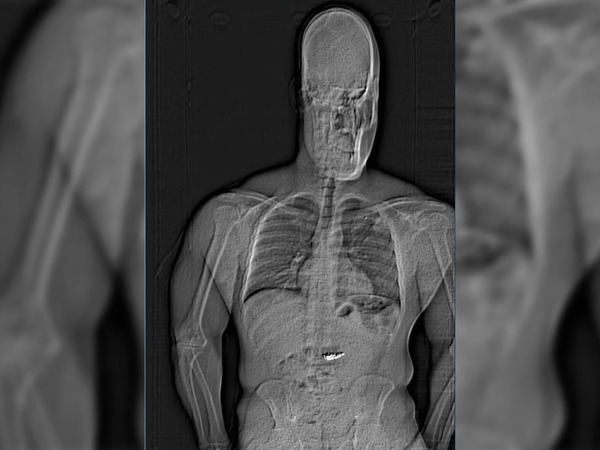

Η αστυνομία κυκλοφόρησε αργότερα μια ακτινογραφία που δείχνει ένα ξένο αντικείμενο μέσα στο στομάχι του δράστη. Σε ερώτηση του BBC, το αστυνομικό τμήμα του Ορλάντο δεν διευκρίνισε αν οι άνδρες του είχαν καταφέρει να ανακτήσουν τα κοσμήματα.